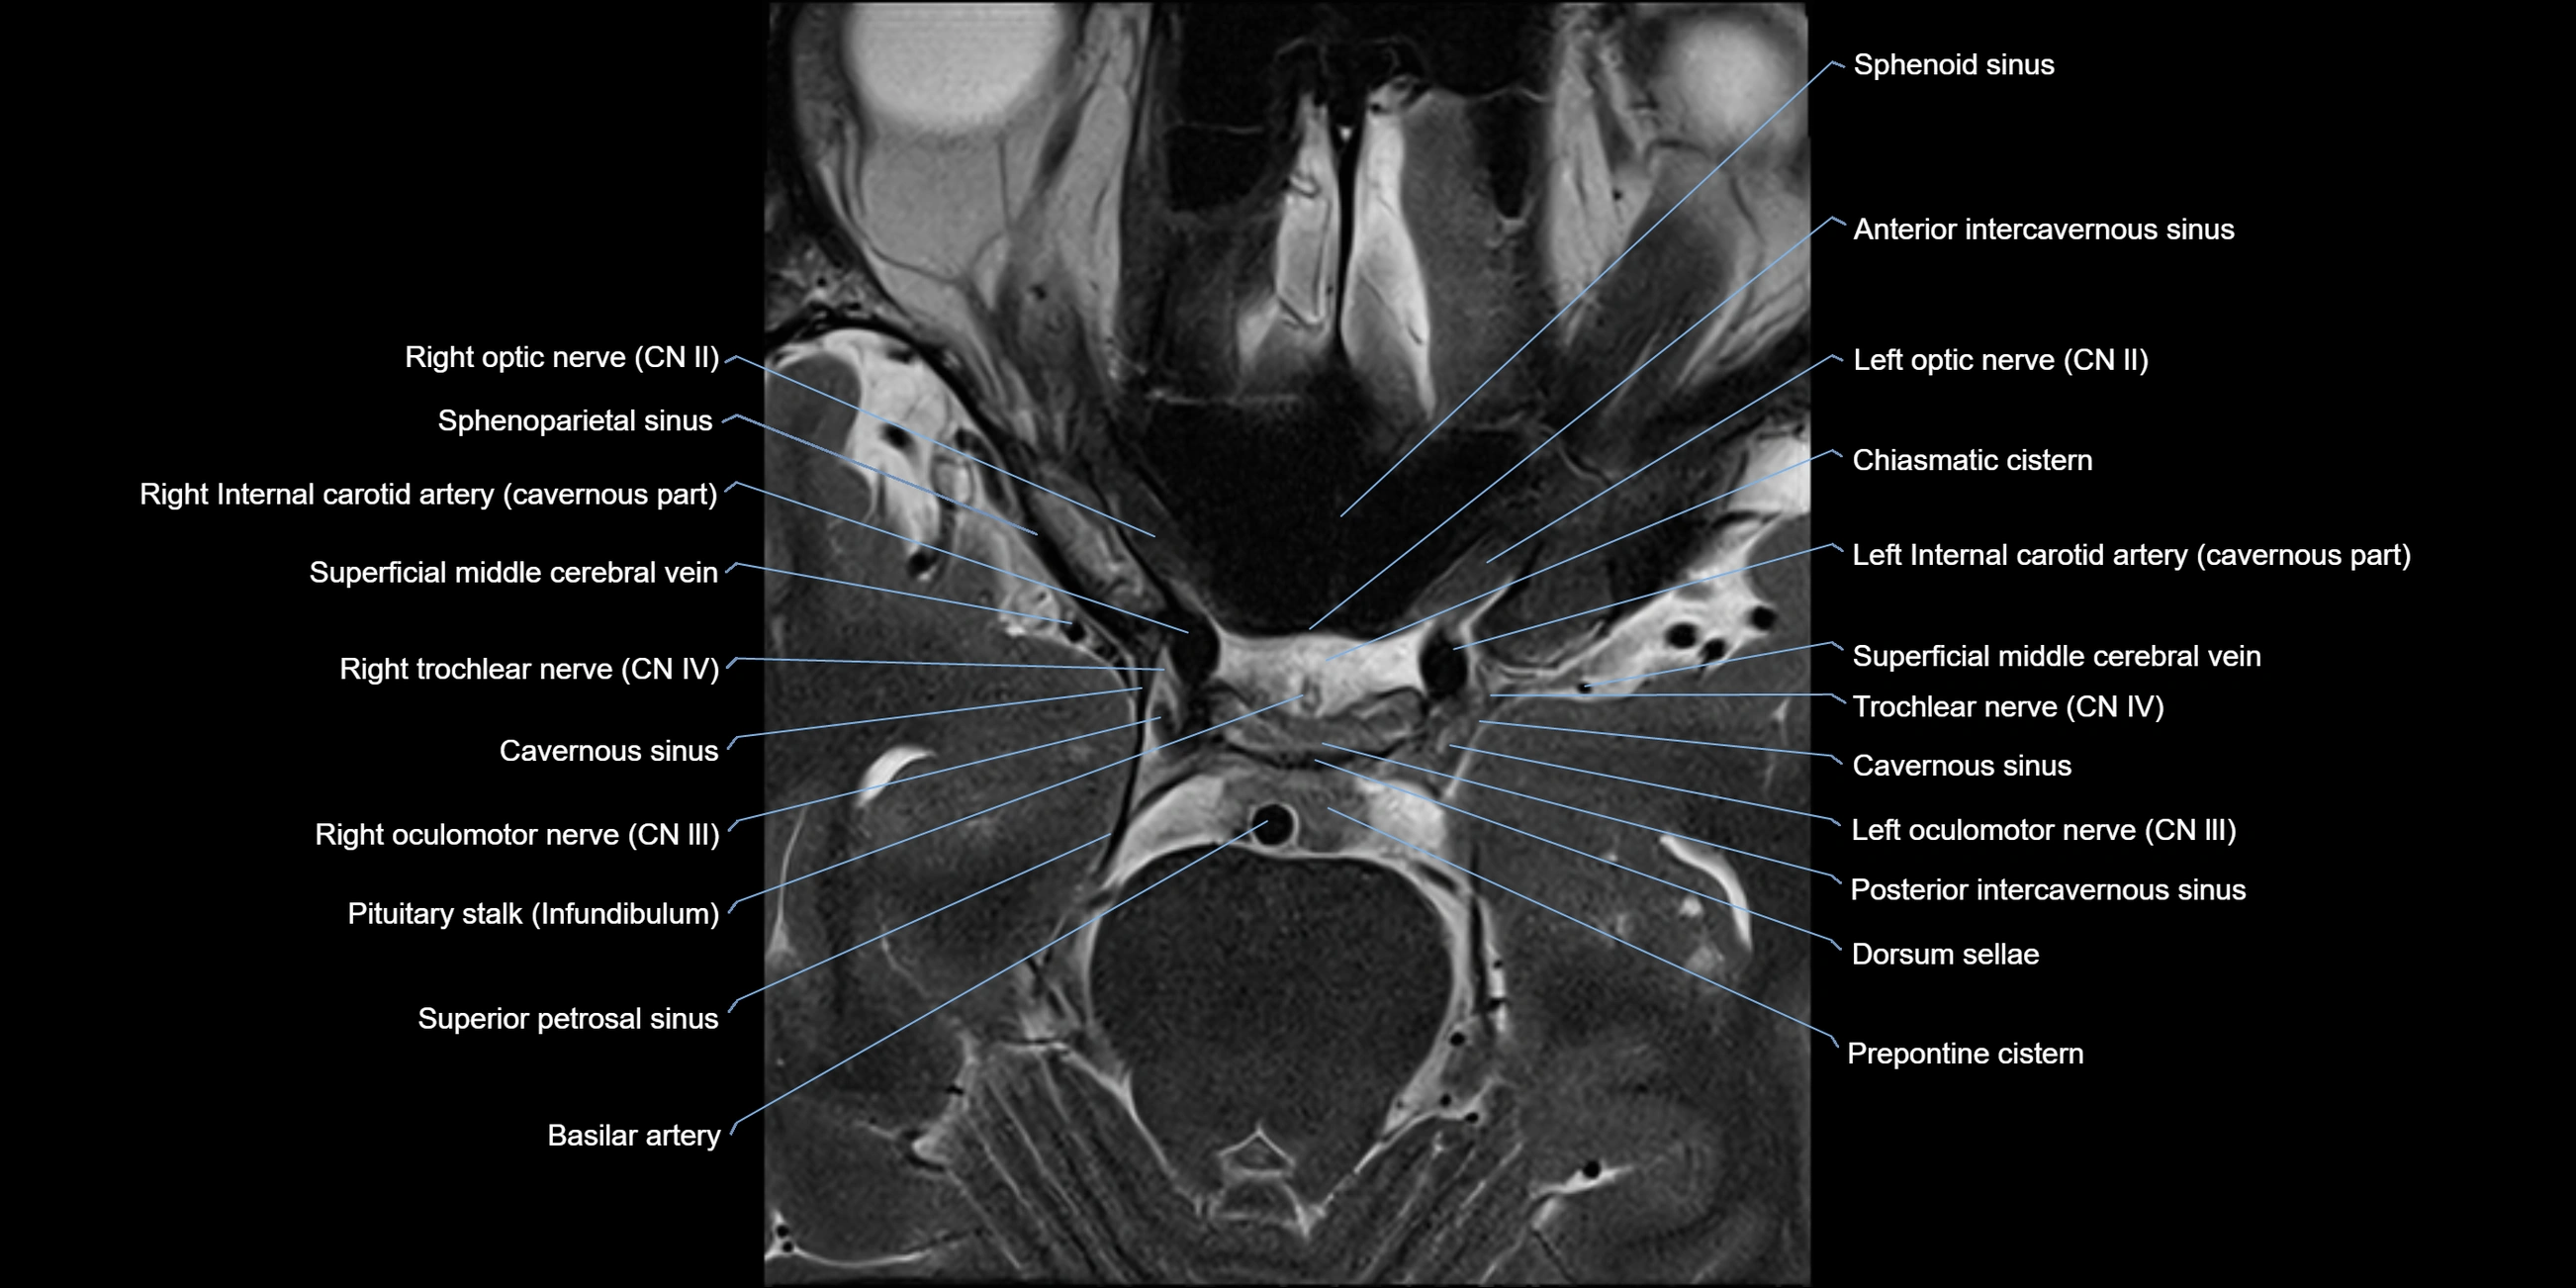

MRI images